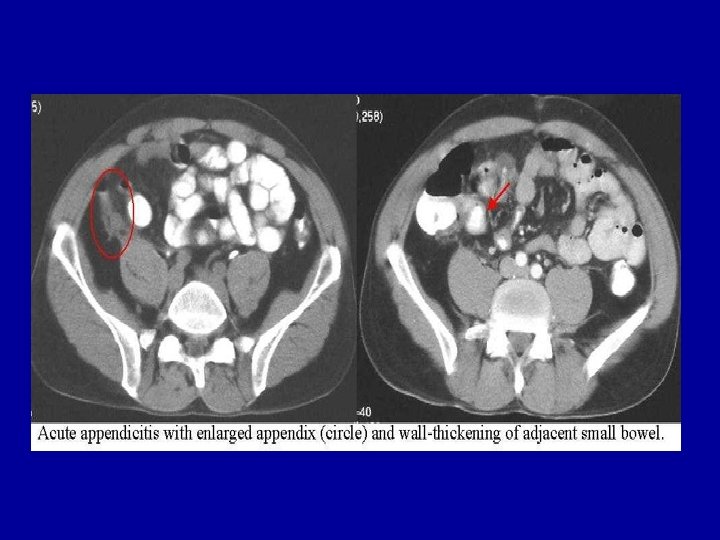

Examen tomodensitométrique abdominal